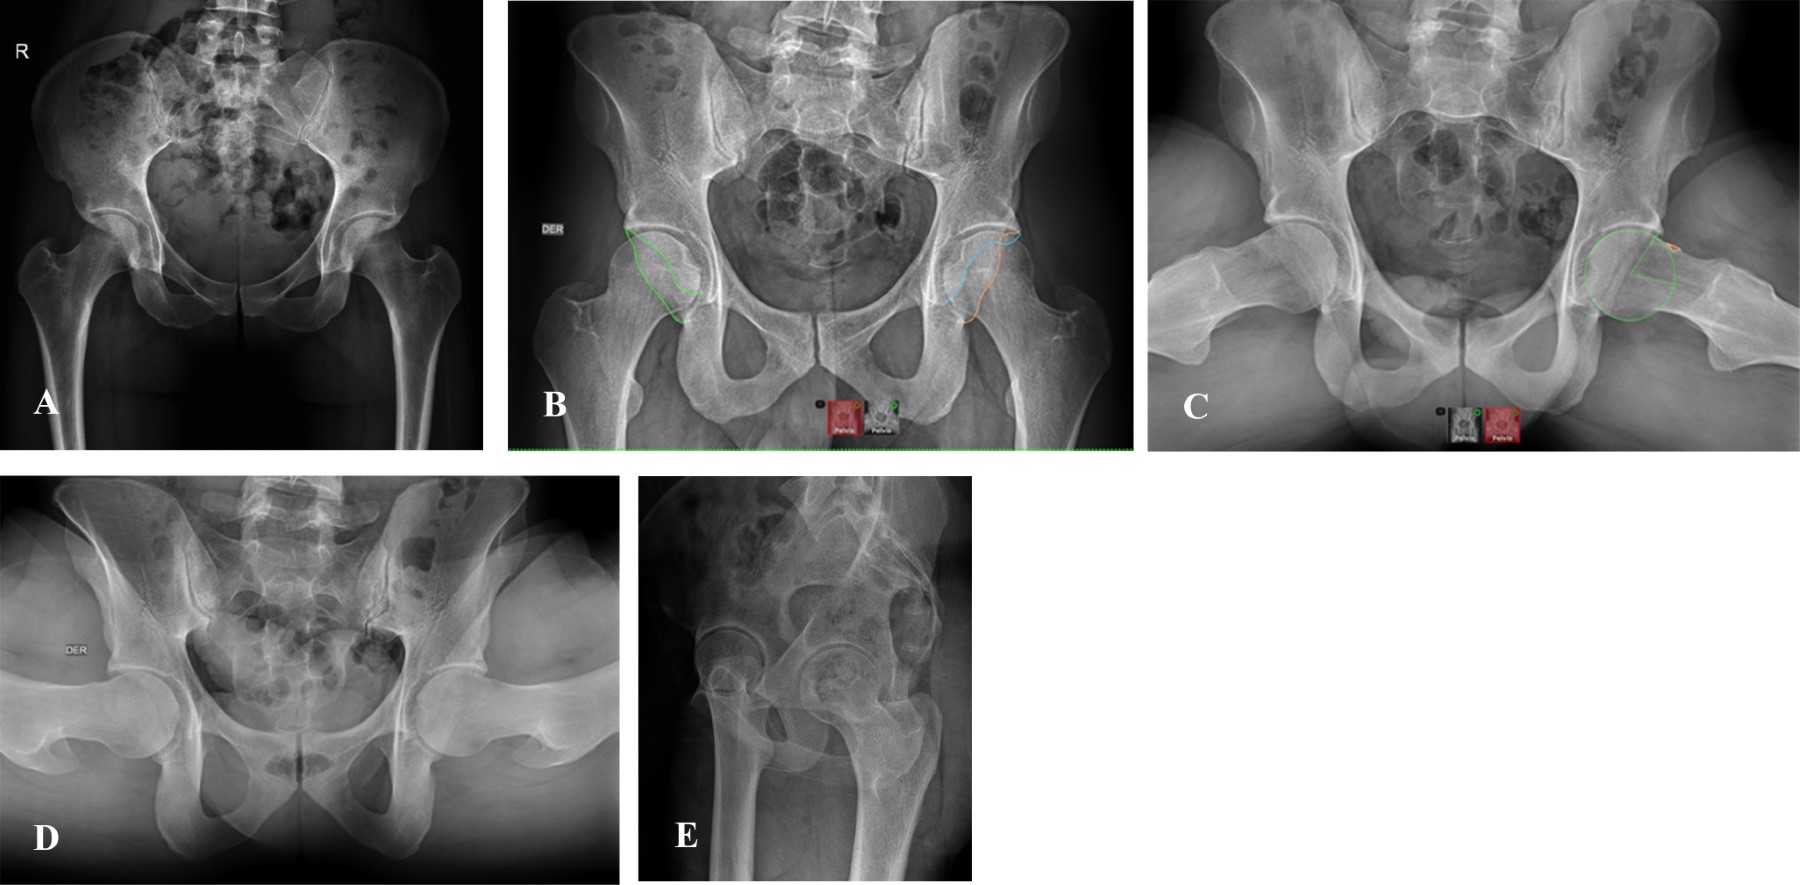

Figure 4

The painful hip has been a topic of study that has evolved from the beginning of the last century to the present. The clinical approach is complex, and requires a systematization process associated with good questioning, clinical maneuvers with their corresponding interpretation, and complementary imaging studies. The understanding of hip pathology, especially in young adults, is highly simplified and sometimes underdiagnosed, therefore, not treated in a timely manner. The prevalence of painful hip is more common in males (49 to 55%) than in females (25 to 28%), and the causes may vary according to demographic characteristics and the history of each patient. Bryan Kelly, made a topographic and anatomical description of the approach to the painful hip according to the theory or system of the layers: I. Osteochondral layer; II. Inert layer; III. Contractile layer; and IV. Neuro-mechanical layer. This system helps us understand the anatomical site of pain and its clinicopathological correlation. The semiological approach to hip pain is the fundamental pillar for differential diagnosis. We can divide it according to its topography into anterior, lateral and posterior, as well as according to its chronology and characteristics. The physical examination should be carried out systematically, starting from a generalized inspection of gait and posture to the evaluation of specific signs for alterations in each layer, which evoke pain with specific postures and ranges of mobility, or weakness and alterations in the arc of mobility of the joint. Image evaluation is initially recommended with radiographic projections that evaluate different planes, both coronal, sagittal and axial, complemented with panoramic views, and eventually dynamic sagittal ones if necessary. Requesting specific studies such as tomography to evaluate bone structure and reserve, or simple MRI when there is suspicion of soft tissue affection, or failing that, arthroresonance for joint pathology, will depend on the clinical symptoms and radiographic findings.